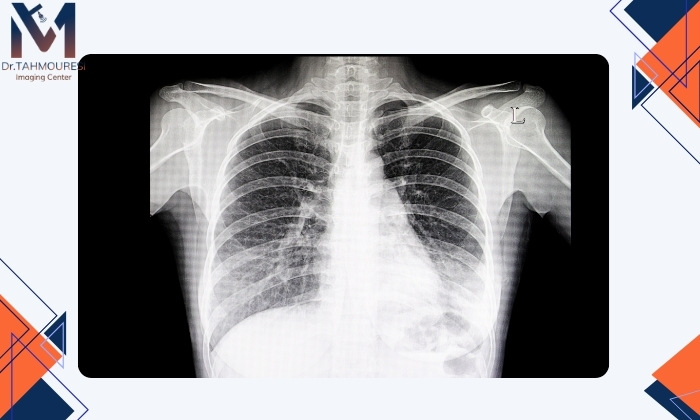

رادیوگرافی قفسه سینه (X-ray): رادیوگرافی قفسه سینه یکی از رایج‌ترین و مؤثرترین روش‌های تشخیص ذات‌الریه است. در این تست تصاویری از ریه‌ها گرفته می‌شود که پزشک می‌تواند علائم التهاب یا تجمع مایعات در ریه‌ها را شناسایی کند. این تست می‌تواند به تعیین محل دقیق عفونت کمک کرده و تفاوت‌های بین ذات‌الریه و دیگر بیماری‌های تنفسی را نشان دهد. اگر قصد انجام رادیولوژی در فردیس کرج را دارید می‌توانید به مرکز تصویربرداری دکتر موسی طهمورسی مراجعه کنید.